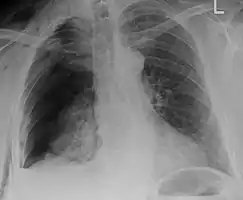

| An X ray showing multiple old fractured ribs of the person's left side as marked by the oval | |

Illustration showing rib fracture at 3rd, 4th and 5th rib Right sided pneumothorax and rib fractures

Right sided pneumothorax and rib fractures Two broken ribs as seen on parasagittal CT